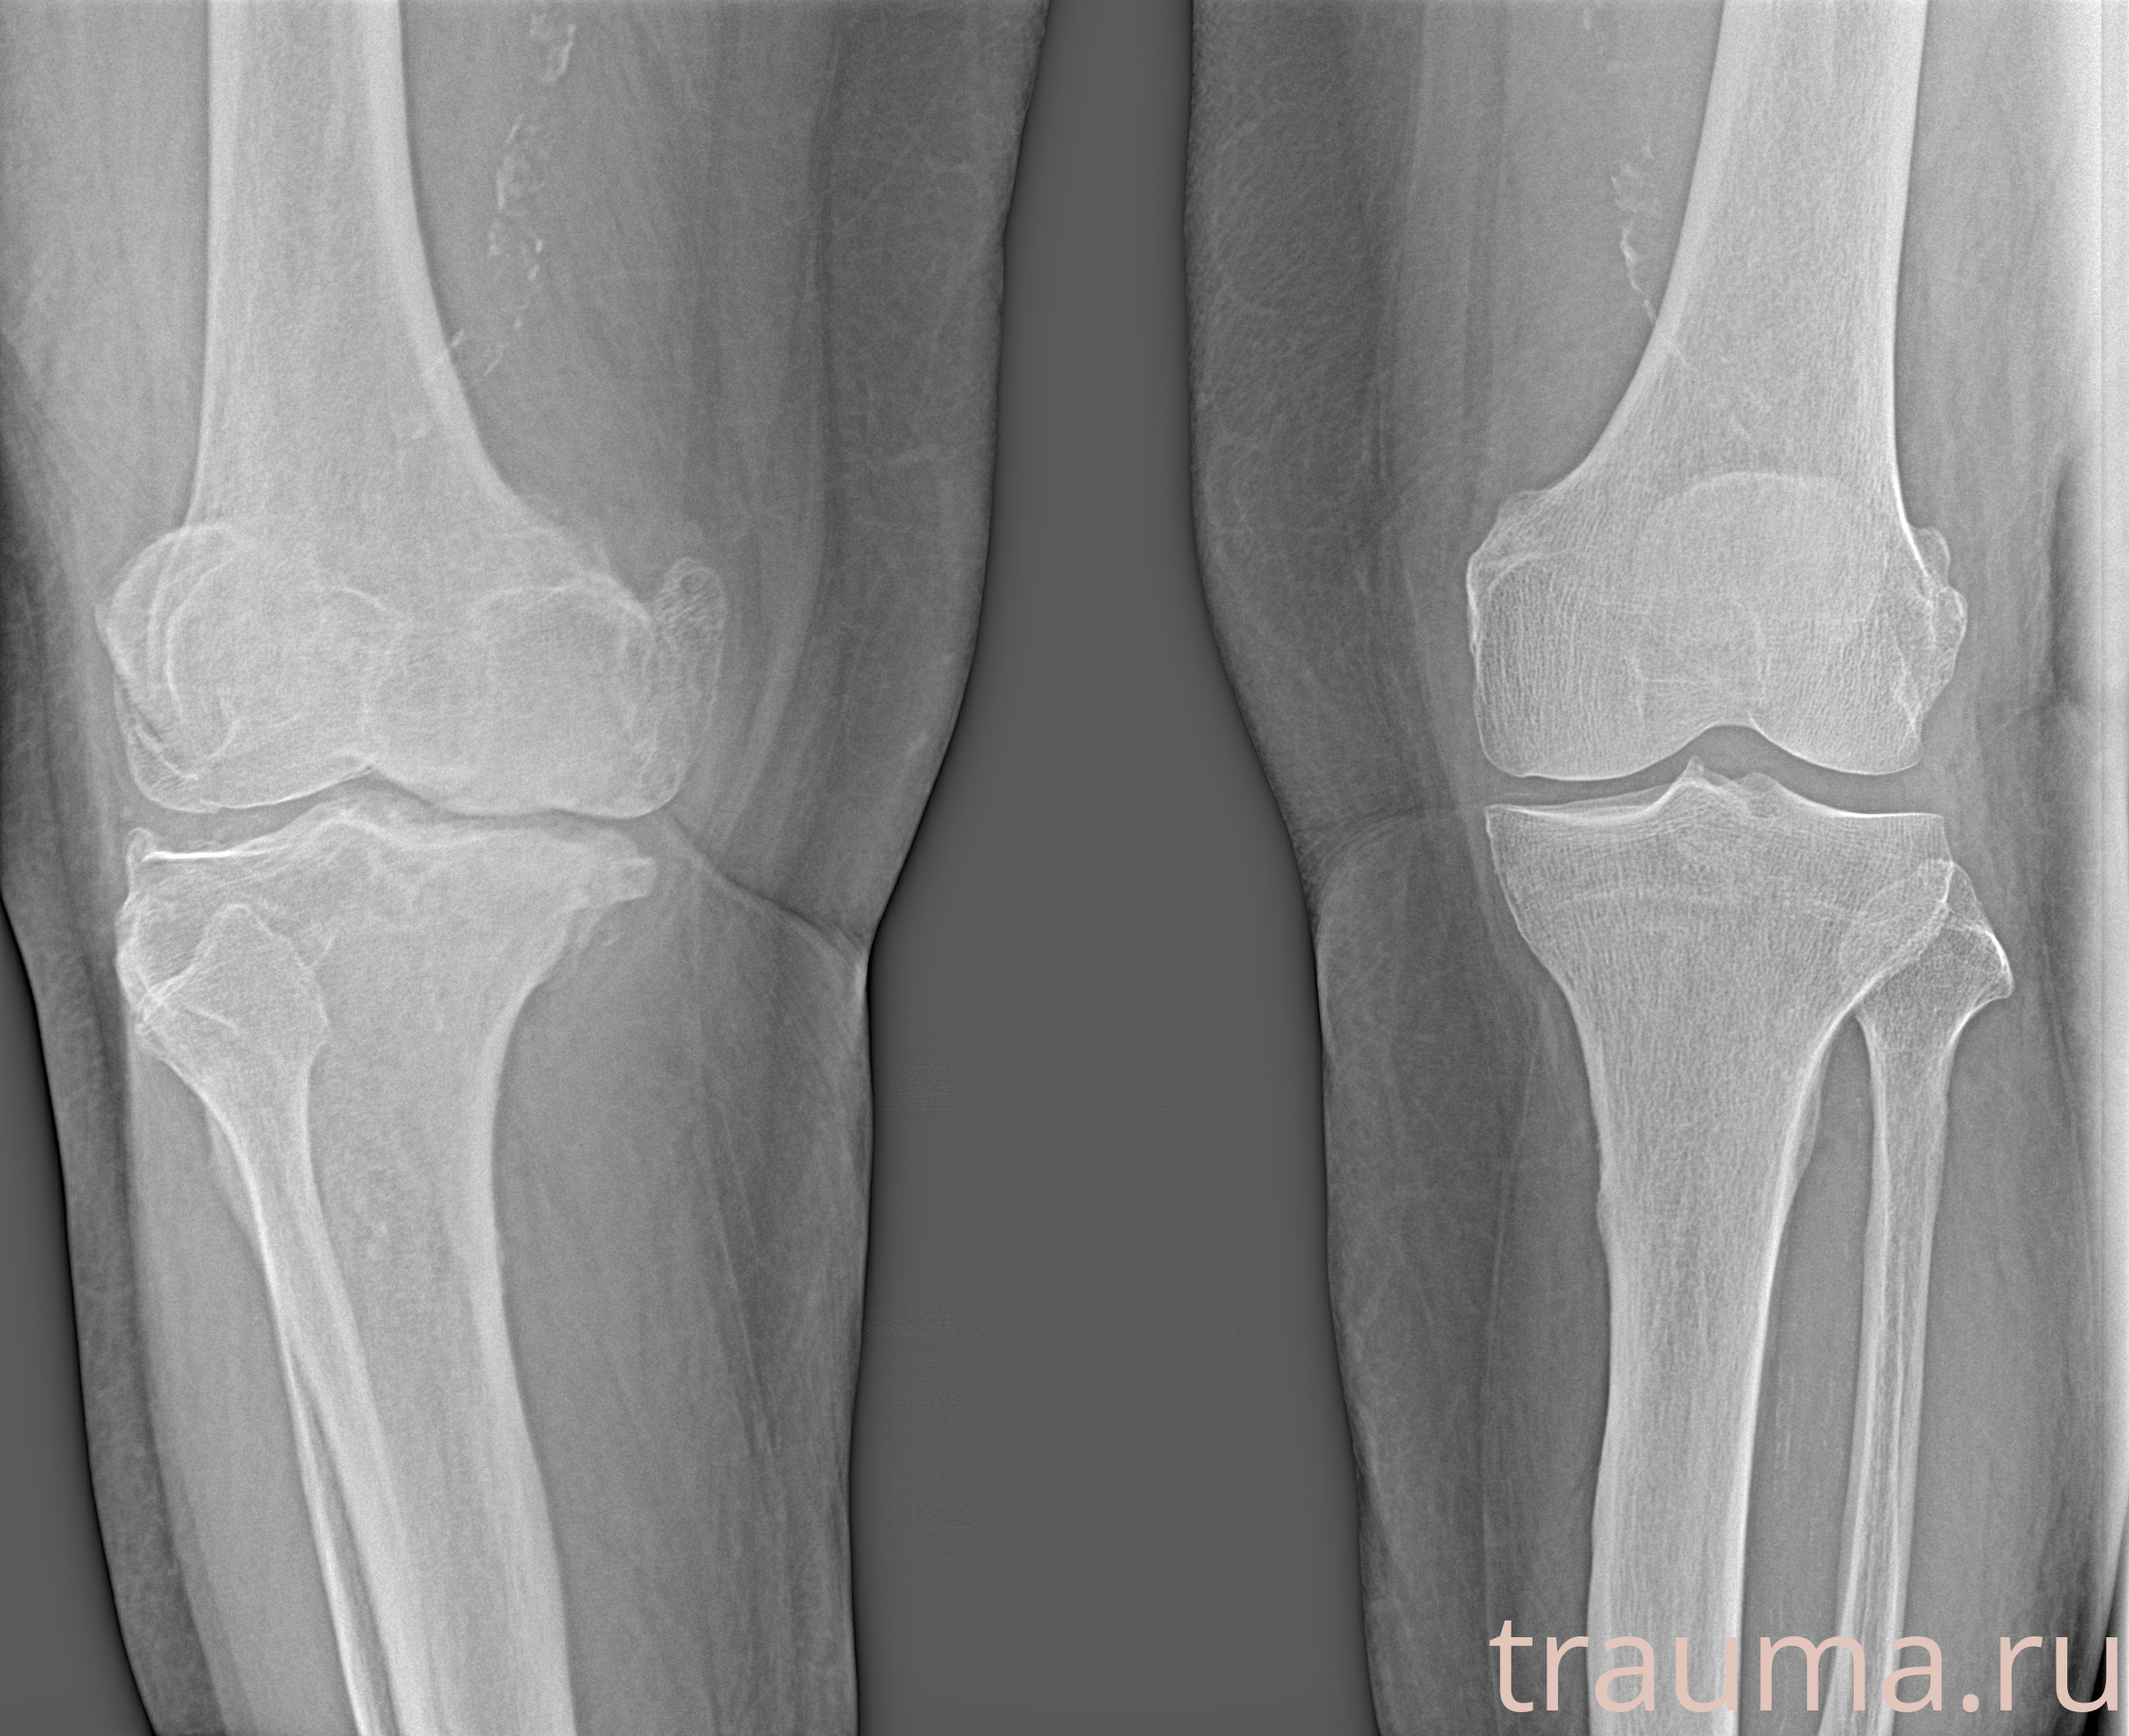

Рентгенограммы